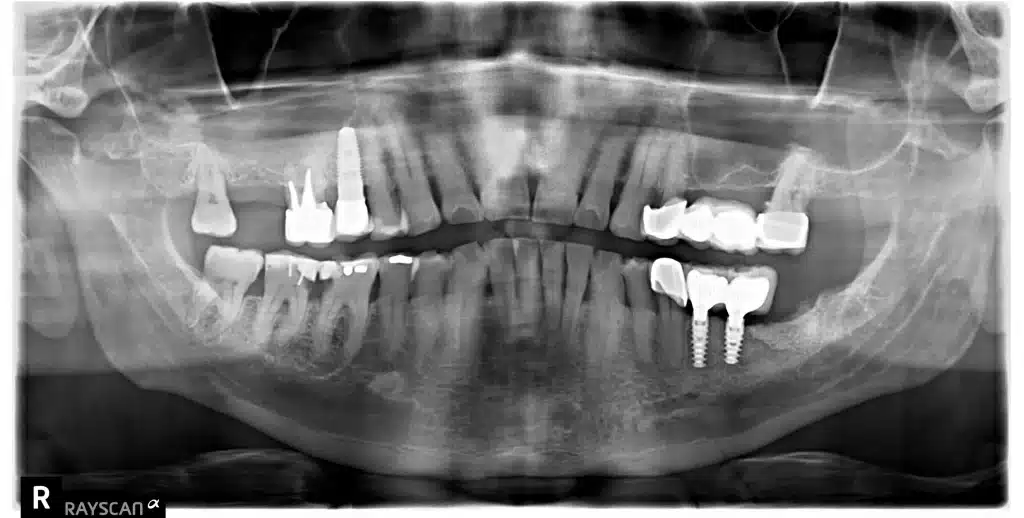

- Una radiografía panorámica para evaluar la densidad ósea y determinar la ubicación de las estructuras anatómicas importantes.

Antes de la cirugía, se realiza una planificación 3D exhaustiva con tecnología de imagen avanzada para diseñar el implante dental. De esta manera, se determina la ubicación precisa del implante y se crea una guía quirúrgica impresa en 3D para su colocación. Esta guía, que se ajusta a los dientes del paciente, ayuda a colocar correctamente el implante dental.

Previo a la cirugía, se administra anestesia y sedación consciente para garantizar una operación sin dolor para el paciente. Posteriormente, se utiliza la guía quirúrgica impresa en 3D para colocar el implante con precisión en el hueso de la mandíbula o el maxilar superior.

imagen obtenida de Ziacom del siguiente enlace, te ivitamos a conocer sus productos. Ziacom es la marca comercial de los implantes de colocamos en clínica dental Nin